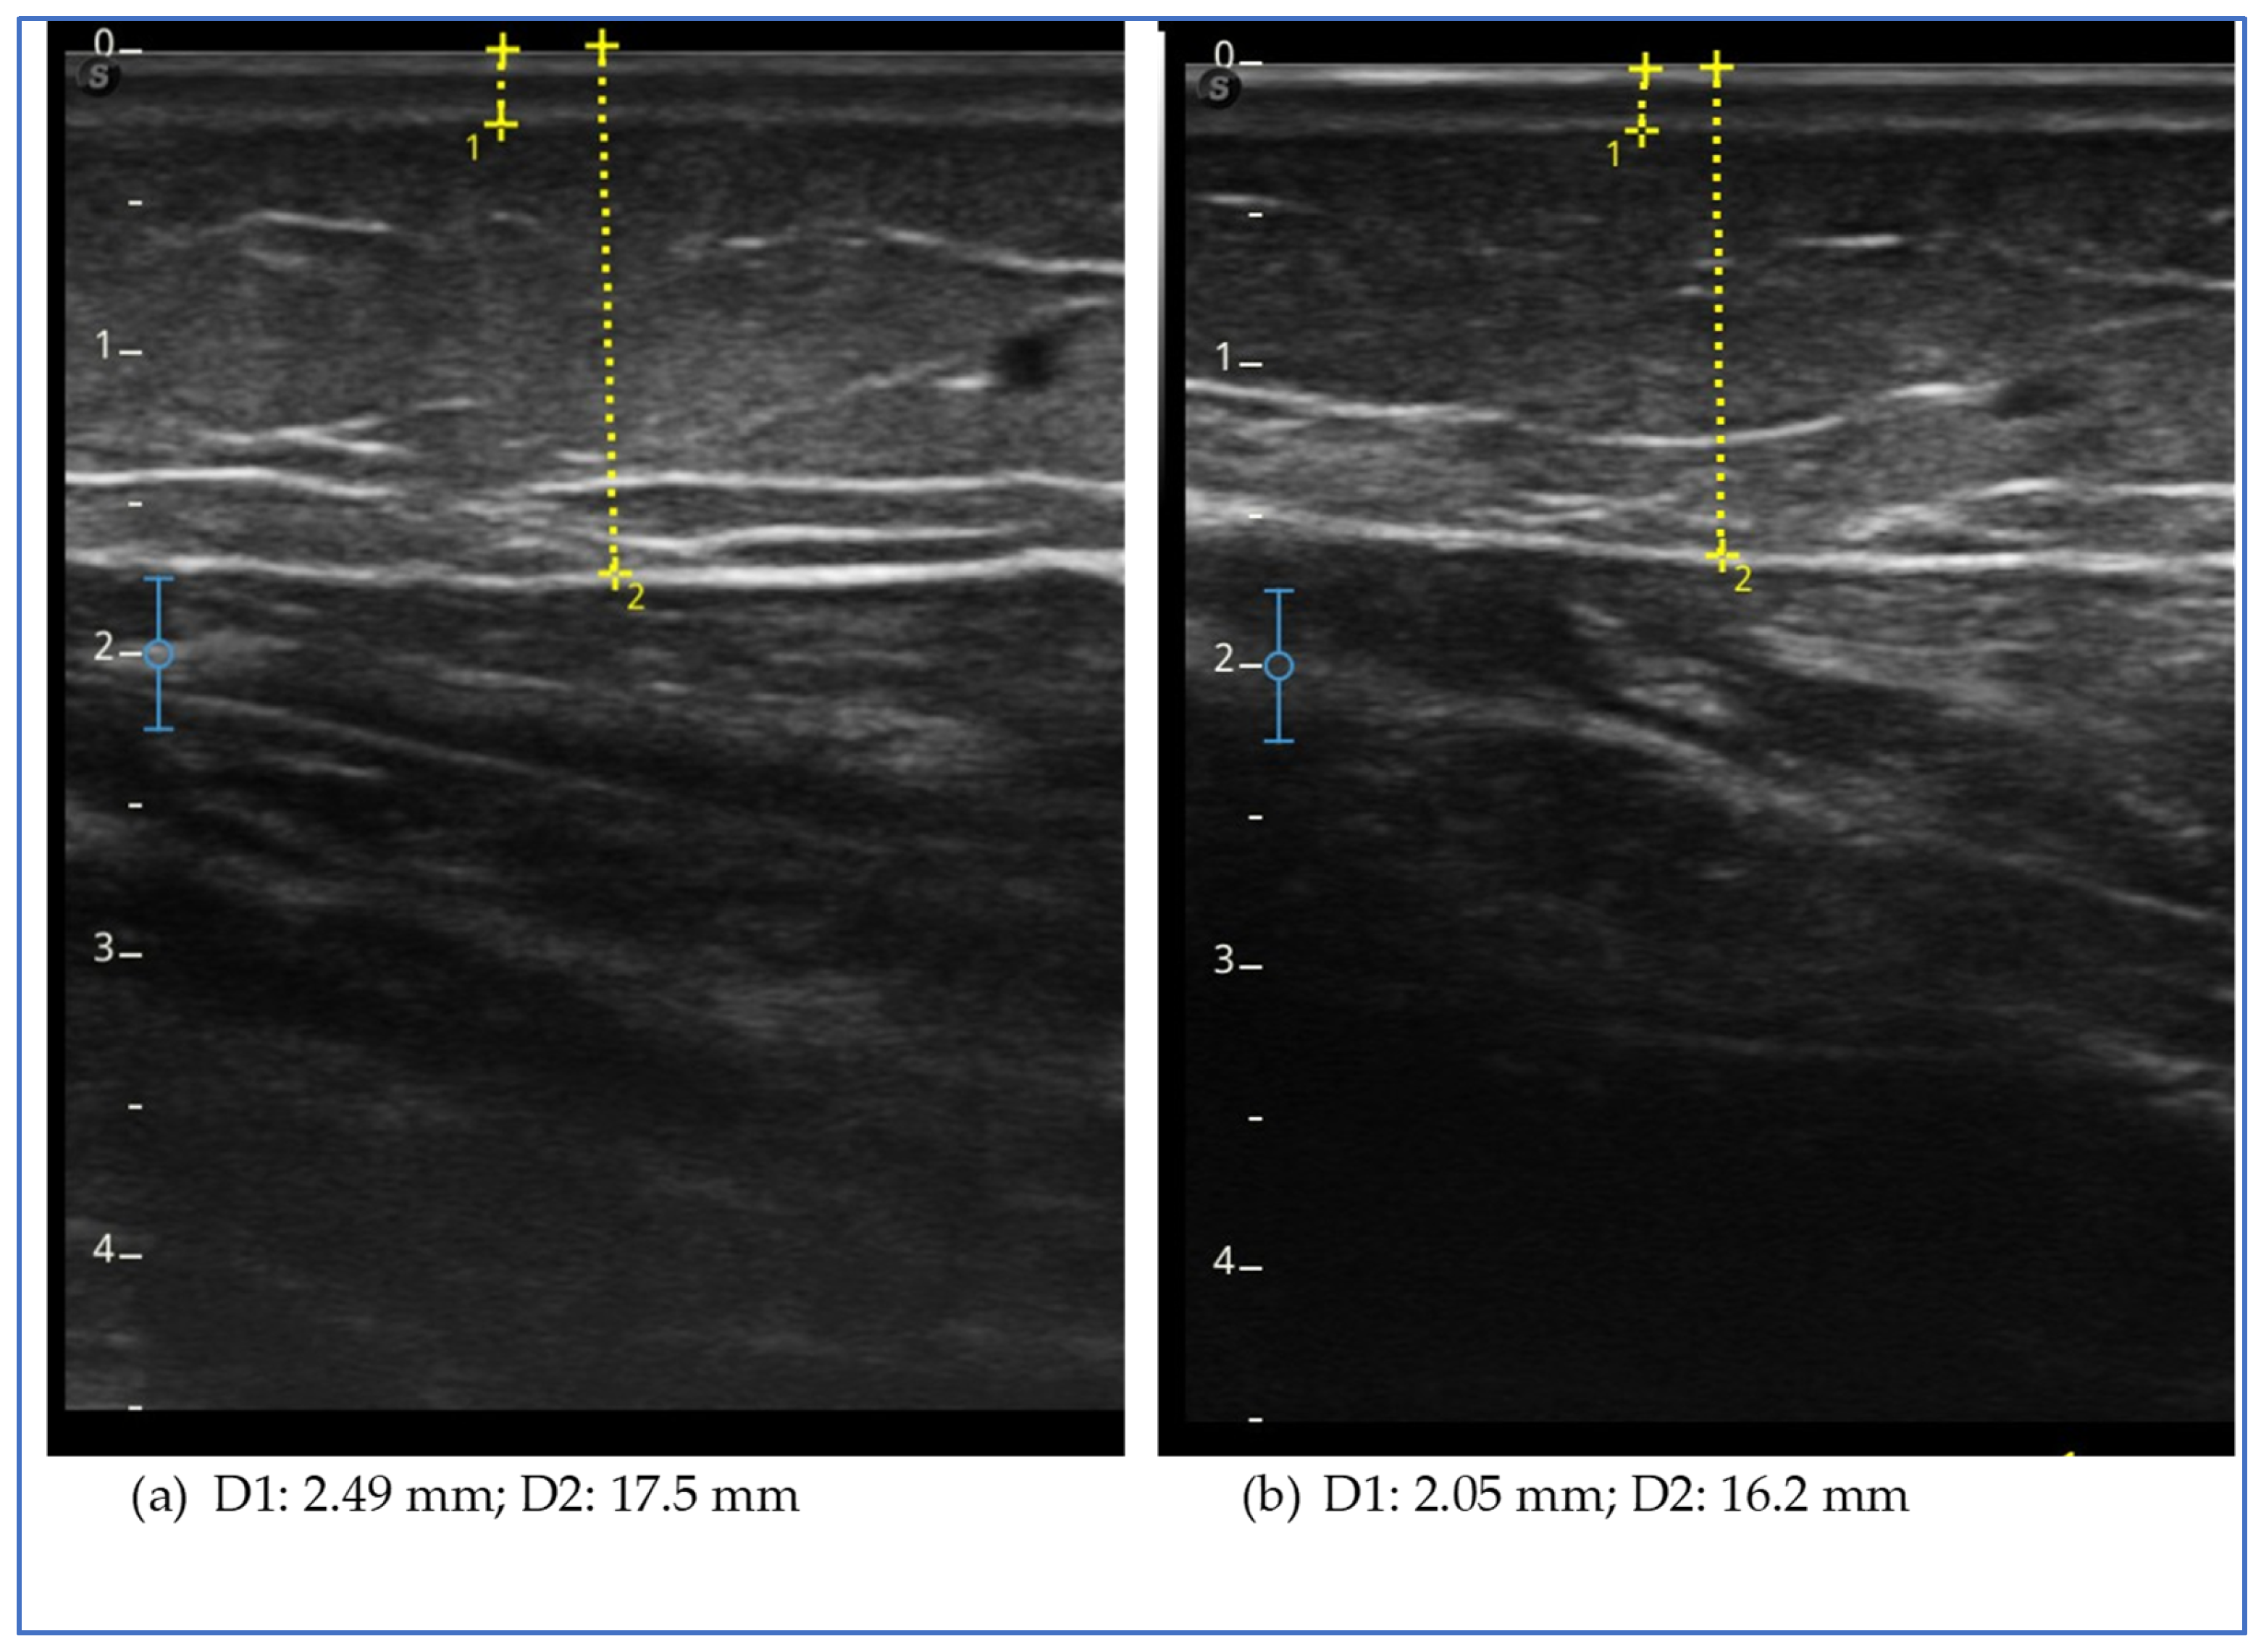

Ultrasound evaluation showed a reduction in subcutaneous fat tissue thickness in the lower extremities, in the abdomen and in the upper extremities, except for the arm, where it increased (Figure 1).

The figure shows the ultrasound measurements at the beginning of the study (a) and at the end of the study (b) of case report 1. The images refer to the anterior middle third of the thigh. The yellow dotted line represents the measurement of the thickness of the skin, which includes the dermal and epidermal layer (D1), and of the subcutaneous adipose tissue (D2), which includes all the tissue from the skin to the muscular fascia of the rectus femoris.

Ultrasound evaluation showed a reduction in the thickness of the subcutaneous adipose tissue in all assessed levels of the lower and upper limb, except the lateral lower third of the thigh (Figure 2). We observed a reduction in thickness in the lower abdomen but an increase in the upper abdomen.

The figure shows the ultrasound measurements at the beginning of the study (a) and at the end of the study (b) for case report 2. The images refer to the lower medial third of the leg. The yellow dotted line represents the measurement of the thickness of the skin, which includes the dermal and epidermal layers (D1), and of the subcutaneous adipose tissue (D2), which includes all the tissue from the skin to the muscular fascia.